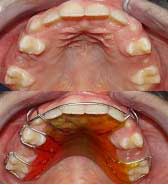

فضانگهدار

اگر دندانهای شیری زودتر از موقع کشیده شود دندانهای طرفین به سمت فضای خالی حرکت کرده با تنگ شدن فضا، باعث رویش نامرتب دندانهای دائمی زیرین می شود و چنانچه افتادن دندانهای شیری دیرتر از موقع اتفاق افتد وجود دندانهای شیری به عنوان مانع ممکن است باعث تأخیر رویش وکج شدن دندانهای دائمی شود. برای جلوگیری از چنین پیشامدی بایستی دندانهای شیری تا زمان رویش دندان دائمی زیر آن با مراجعه به دندانپزشک و انجام اقدامات لازم حفظ و نگهداری شود و در موارد ضروری پس از کشیدن دندان شیری با قالب گیری و ساخت وسیله ای بنام فضانگهدار توسط دندانپزشک که به دو صورت ثابت و متحرک ساخته می شود، رویش منظم دندانهای دائمی تضمین می گردد.